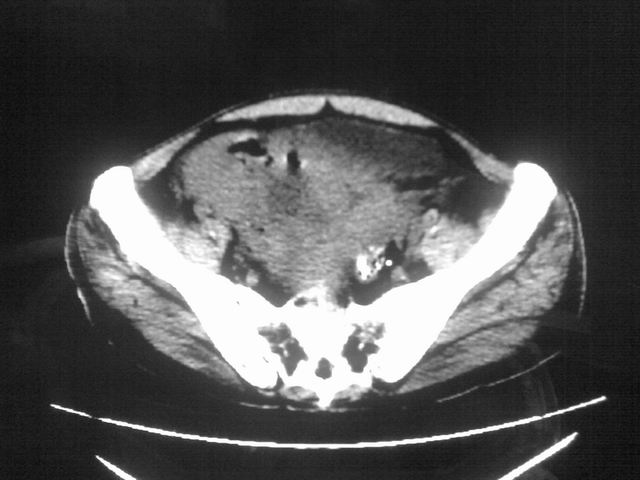

患者m 56岁,盆腔及下腹部胀痛半年,加重1月余,消瘦\中重度贫血.(附:平扫时直肠的高信号为,残留的钡剂).补一下病史:胃镜及纤维结肠镜均无明显异常.

首先是病灶的定位,平扫看很象肠管肿瘤但既然纤维结肠镜正常就可以除外结肠病变,增强成不均匀强化,位于右下腹部应该首先考虑回肠末段占位性病变,1淋巴瘤,2间质瘤,3腹膜后神经原肿瘤待除外,

膀胱及直肠间有不规侧的软组织密度影,内密度不均匀。其内有坏死囊变,前列腺及精囊腺,膀胱后壁受浸。结合病史考虑腹膜后肉瘤可能性大。

这样的病如果在结肠的话结肠镜应该能发现。既然结肠镜排除了结肠占位,就考虑淋巴瘤或胃肠间质性肿瘤

这样的病如果在结肠的话结肠镜应该能发现。既然结肠镜排除了结肠占位,就考虑小肠淋巴瘤或小肠间质性肿瘤恶变?